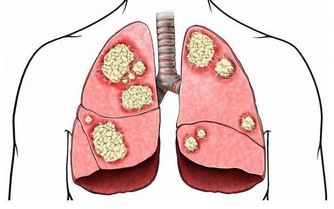

50歲的陳先生因不明原因的咳嗽去醫院就診,誰知道,做完CT檢查,竟發現是肺癌晚期。

為什麼年年體檢,卻查不出早期肺癌?

類似陳先生一樣遭遇的肺癌患者並不在少數。有人甚至將X光查肺癌稱為“最坑爹的體檢項目”,就連不少醫生也表示,用X光片篩查早期肺癌,確實不靠譜。

雖然X光片在臨床應用廣泛,但因分辨率較低,對於微小以及隱蔽部位的病灶,都不易發現到。用其篩查肺癌漏診率相當高,到用X光能夠查出時,多數已是中晚期了。

而實際上,目前醫學界公認篩查早期肺癌最有效的手段是——低劑量螺旋CT,其發現早期肺癌的敏感度是常規胸片的4~10倍,大大提高肺癌的治愈率和存活率。

但不少人擔心用CT檢查輻射大,會對身體造成傷害,實際上肺癌篩查用的不是CT的常規劑量,其射線量僅為普通CT的1/6,不必過於擔心輻射的問題。

六類高危人群,最好每年查CT

建議50歲左右,尤其是以下肺癌的高發人群,每年最好做一次CT檢查。